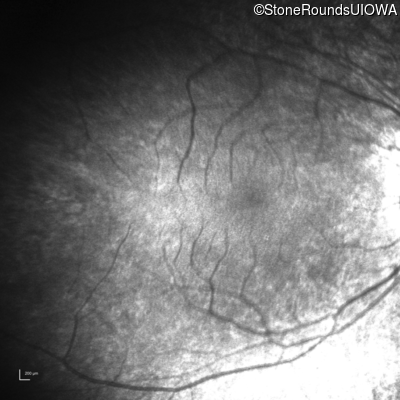

Infrared Fundus Photograph - Right - Light Perception

Exemplar